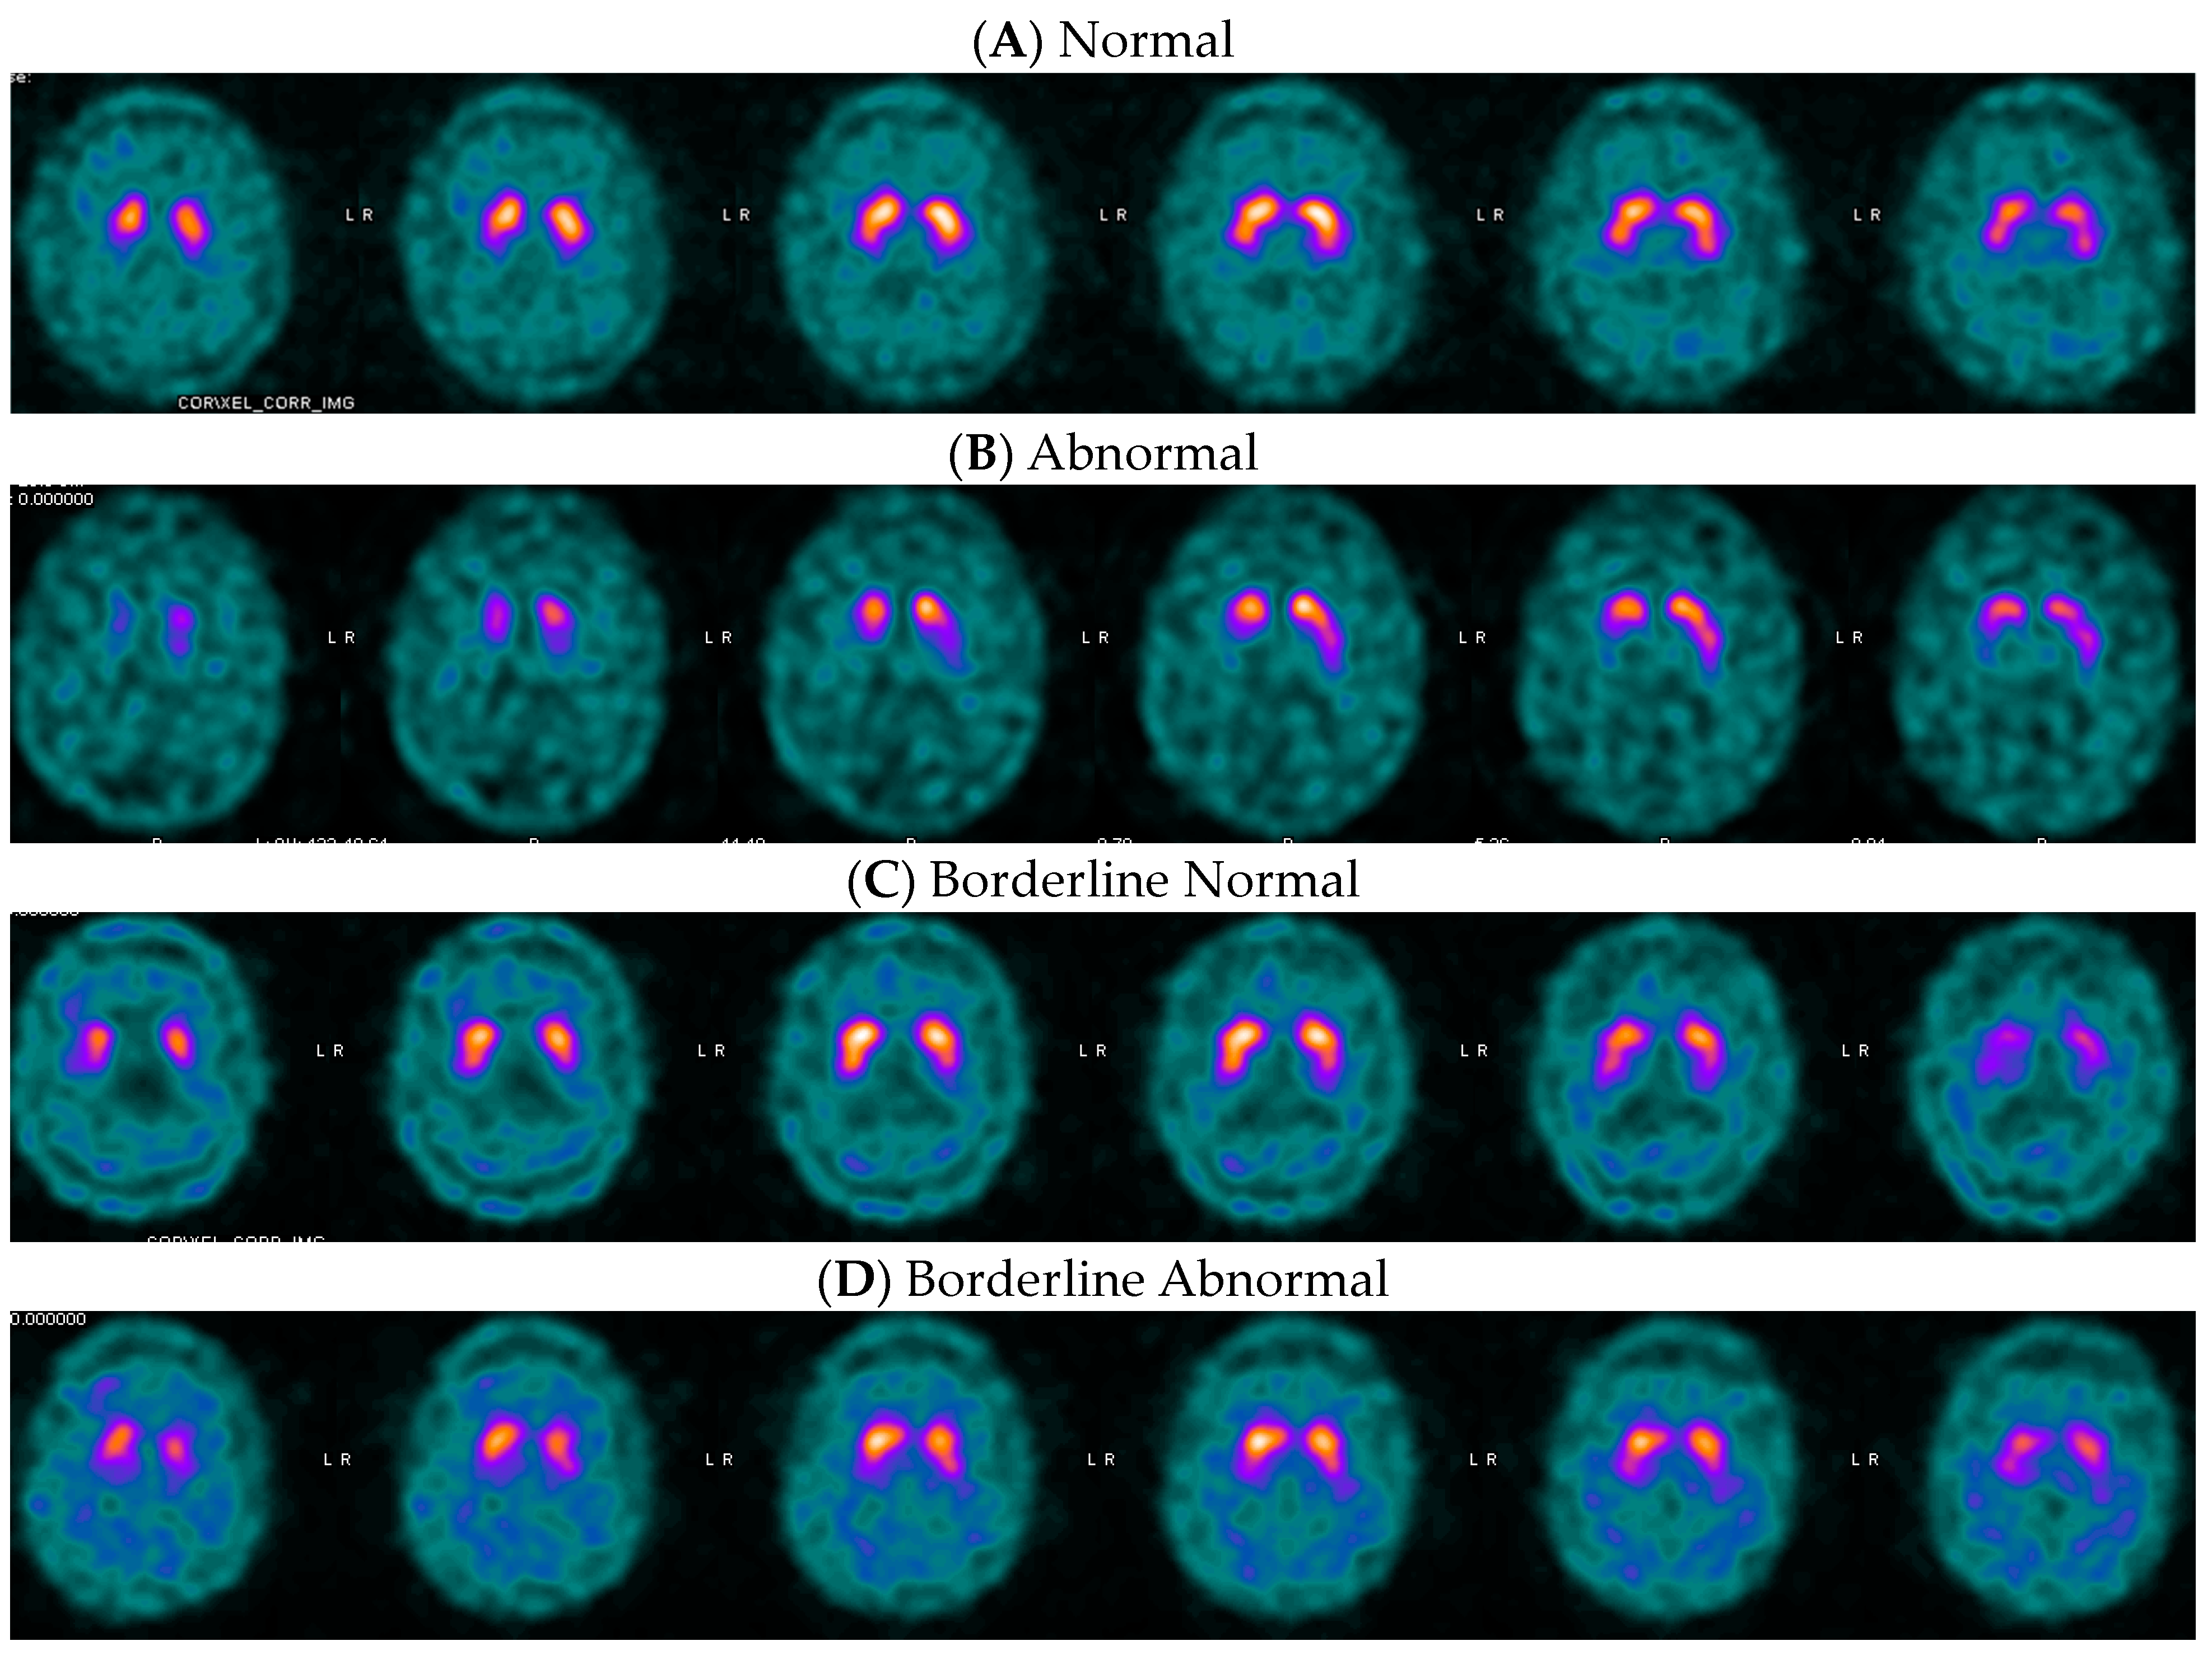

Frontiers in Parkinson Disease 2015年8月号(Vol.8 No.3。Optimal DaTQUANT Thresholds for Diagnostic Accuracy of。Frontiers | Identification of necroptosis-related genes in。